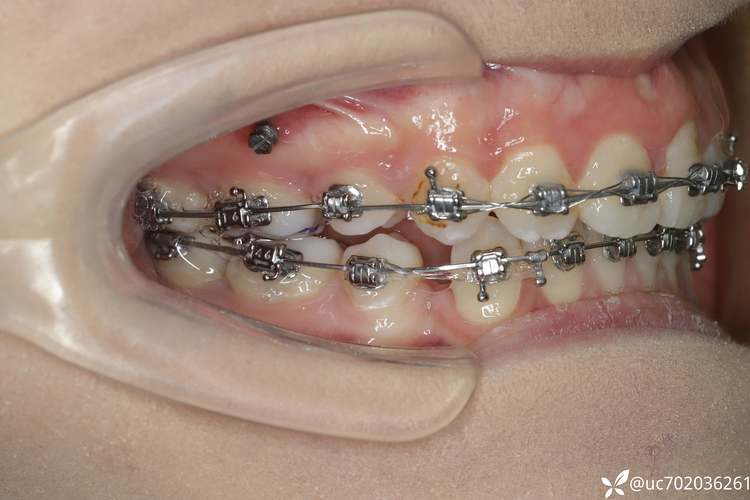

在硬件设施方面,科室配备了国际先进的数字化正畸诊疗系统,包括德国Sirona口腔CBCT、美国iTero口内扫描仪、3D打印技术及计算机辅助设计(CAD/CAM)设备,实现了从检查、诊断到方案设计的全程数字化,通过数字化口扫,可在10分钟内获取患者口腔的精确三维数据,避免传统取模的不适感;结合CBCT的影像数据,可清晰观察牙齿、牙根及颌骨的立体结构,为埋伏牙、骨性错颌等复杂病例的精准诊断提供保障,科室还引入了多种矫治技术体系,涵盖传统金属托槽、陶瓷托槽、自锁托槽、隐形矫治以及舌侧矫治等,满足不同年龄段、不同美观需求患者的治疗要求。

核心技术与服务特色方面,科室在骨性错颌的早期干预、成人正畸-修复联合治疗、阻生牙牵引等领域形成独特优势,针对青少年患者,科室主张“早期干预、简化治疗”的理念,对于骨性反颌(地包天)、开颌、深覆颌等问题,在替牙期或恒牙早期通过功能性矫治器(如FRⅢ、Twin Block)或简单固定矫治器进行干预,引导颌骨正常生长,避免成年后复杂的正颌手术,对于成人患者,尤其是伴有牙列缺损、牙体缺损或牙周病的患者,科室正畸团队与修复科、牙周科协作,通过“正畸-修复联合治疗”,在排齐牙齿的同时,为后续的种植牙、烤瓷牙修复创造条件,实现功能与美观的双重修复,在隐形矫治领域,科室是宁夏地区首批开展隐适美(Invisalign)、时代天使等隐形矫治技术的单位,结合数字化方案设计,可实现牙齿移动的精准预测,患者可在治疗过程中通过3D动画预知矫正效果,治疗过程舒适、美观,且可自行摘戴,便于口腔清洁。

诊疗流程方面,科室建立了标准化的正畸治疗路径,确保每例患者获得系统、规范的治疗,初诊阶段,患者需完成全面的口腔检查,包括口内检查、模型制取、X线片拍摄(全景片、头颅侧位片、CBCT)及面部照片拍摄,医生会综合评估患者的牙齿排列、咬合关系、颌骨发育、面部美观及牙周健康状况,对于复杂病例,科室会组织正畸、颌面外科、修复科等多学科会诊(MDT),制定联合治疗方案,方案设计阶段,医生会结合患者的年龄、主诉及美观需求,在数字化系统中模拟多种牙齿移动方案,与患者充分沟通后确定最终矫治计划,明确治疗周期、费用及注意事项,治疗开始前,需进行必要的牙周治疗(如洁治、刮治)、龋齿充填及拔牙(如需要),为正畸治疗创造健康的口腔环境,矫治过程中,患者需定期复诊(传统矫治通常4-6周一次,隐形矫治6-8周一次),医生会检查牙齿移动情况,调整矫治力,必要时进行附件粘接、弓丝更换等操作,治疗结束后,患者需佩戴保持器,以维持矫正效果,防止复发。